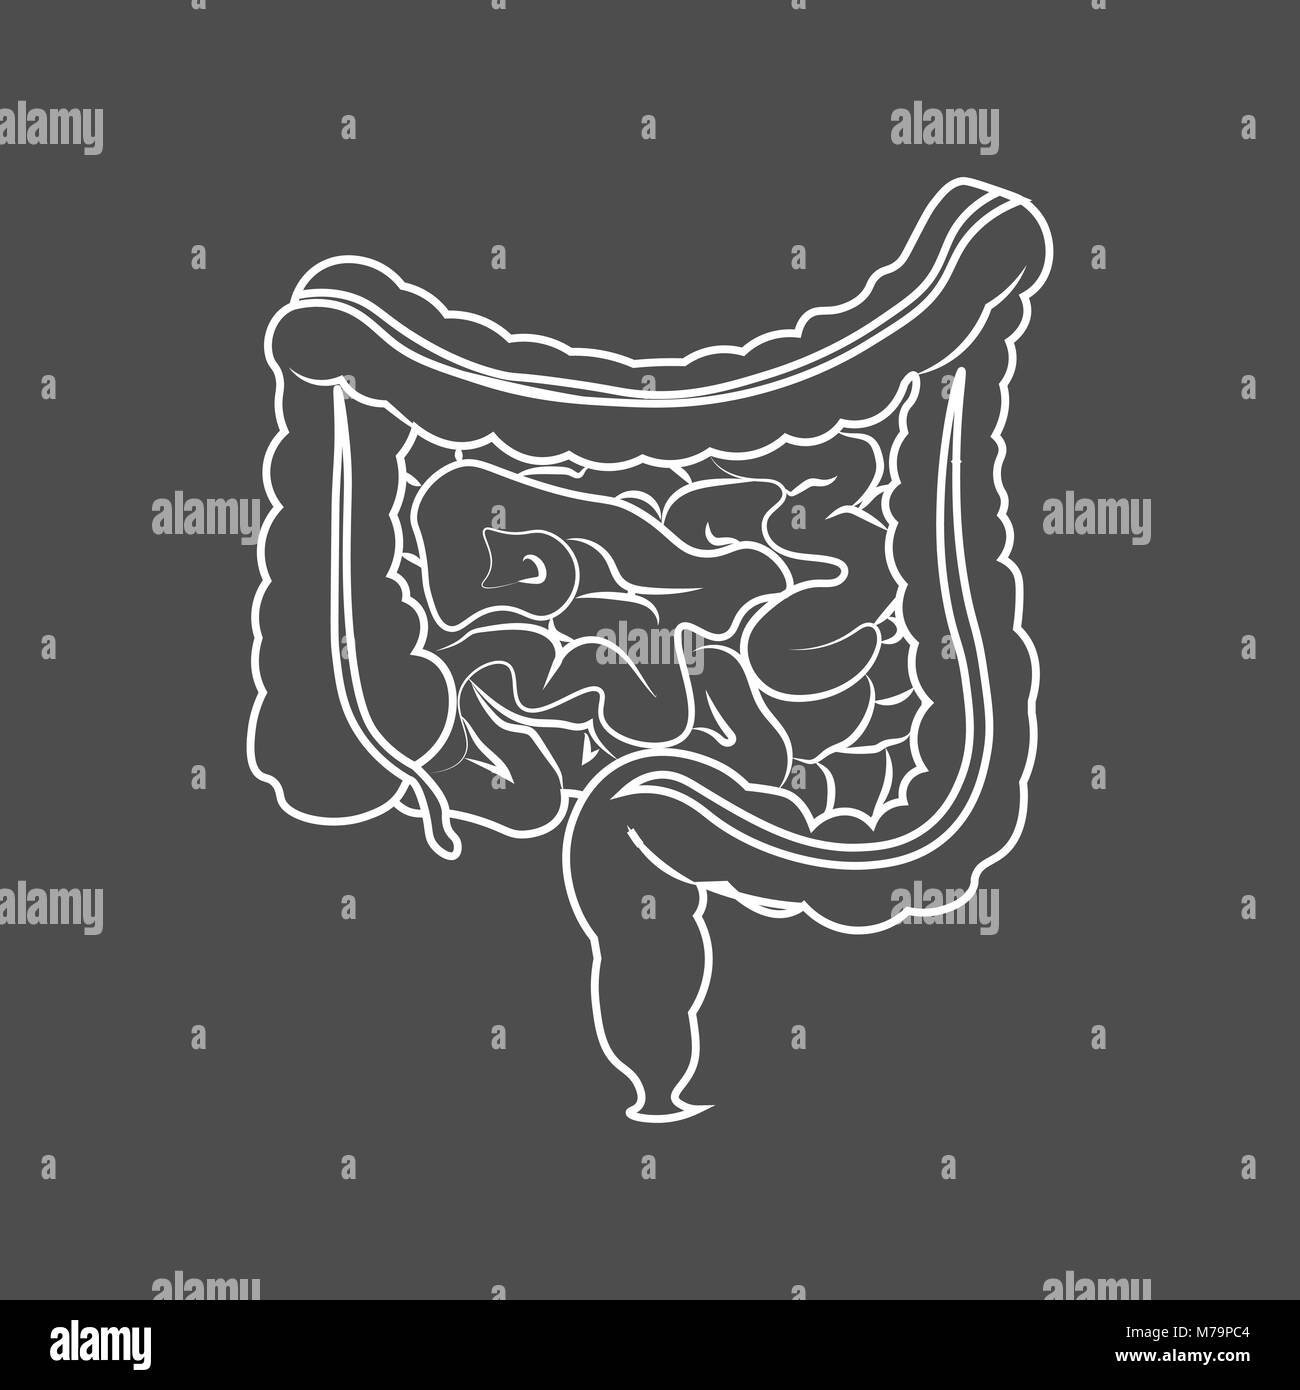

Vector intestines medical contoured illustration, structure of the human colon, internal organ, digestive tract. Stock Vectorhttps://www.alamy.com/image-license-details/?v=1https://www.alamy.com/vector-intestines-medical-contoured-illustration-structure-of-the-human-colon-internal-organ-digestive-tract-image385473402.html

Vector intestines medical contoured illustration, structure of the human colon, internal organ, digestive tract. Stock Vectorhttps://www.alamy.com/image-license-details/?v=1https://www.alamy.com/vector-intestines-medical-contoured-illustration-structure-of-the-human-colon-internal-organ-digestive-tract-image385473402.htmlRF2DB3R76–Vector intestines medical contoured illustration, structure of the human colon, internal organ, digestive tract.

Human digestive system intestines gut anatomy gastrointestinal tract diagram. Monochrome contour of the intestine Stock Vectorhttps://www.alamy.com/image-license-details/?v=1https://www.alamy.com/stock-photo-human-digestive-system-intestines-gut-anatomy-gastrointestinal-tract-176621428.html

Human digestive system intestines gut anatomy gastrointestinal tract diagram. Monochrome contour of the intestine Stock Vectorhttps://www.alamy.com/image-license-details/?v=1https://www.alamy.com/stock-photo-human-digestive-system-intestines-gut-anatomy-gastrointestinal-tract-176621428.htmlRFM79PC4–Human digestive system intestines gut anatomy gastrointestinal tract diagram. Monochrome contour of the intestine